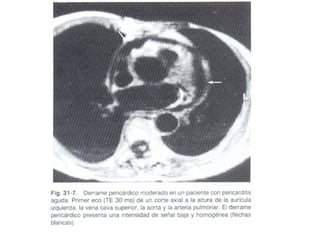

PERICARDITIS AGUDA Clínicamente hay dolor torácico, cambios electrocardiográficos y roce pericárdico. Las causas mas comunes son: idiopática, viral, neoplásica, bacteriana, tbc.

PERICARDITIS AGUDA Clínicamentehay dolor torácico, cambios electrocardiográficos y roce pericárdico. Las causas mas comunes son: idiopática, viral, neoplásica, bacteriana, tbc.